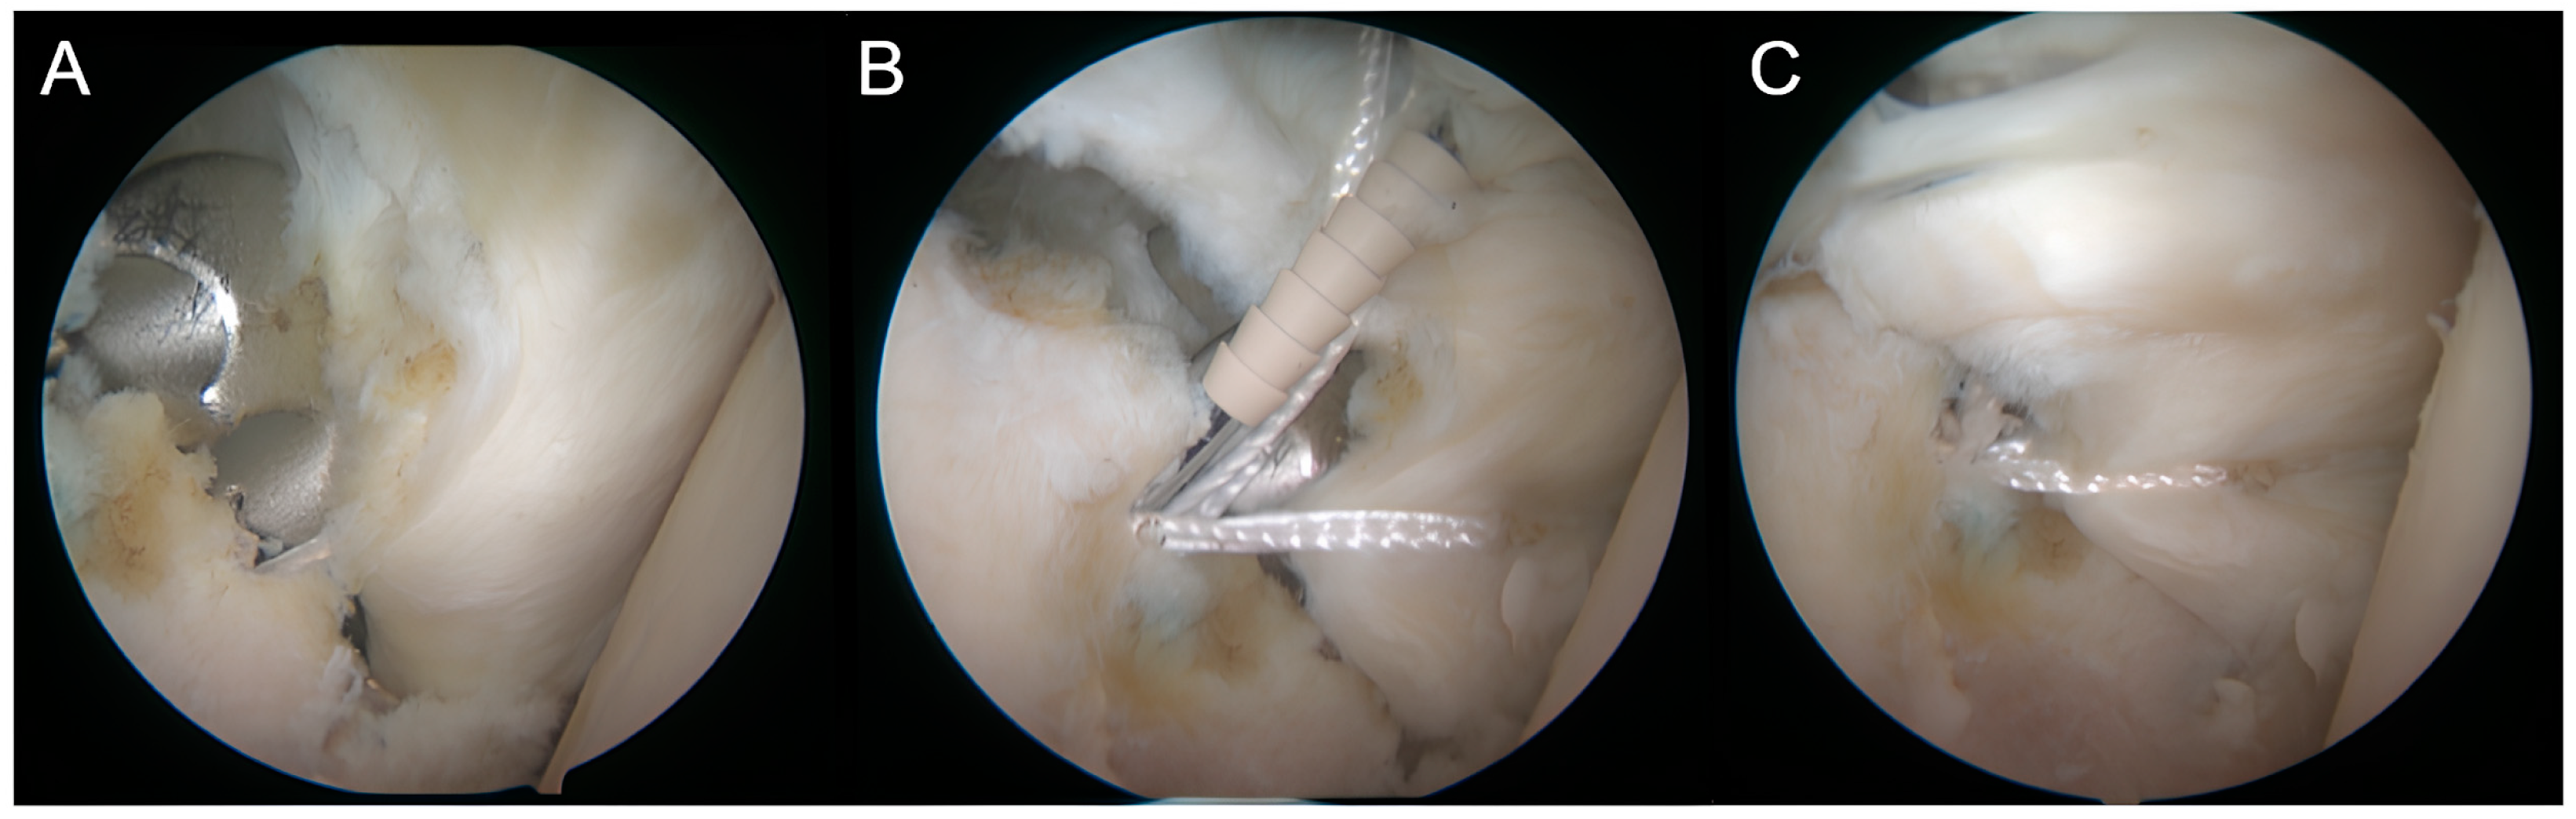

2.7.1. Step 1: Diagnostic Arthroscopy and Anterior Preparation

2.7.2. Step 2: Glenoid Preparation

2.7.3. Step 3: Tunnel Preparation

2.7.4. Step 4: Implant Positioning

2.7.5. Step 5: Bankart Repair